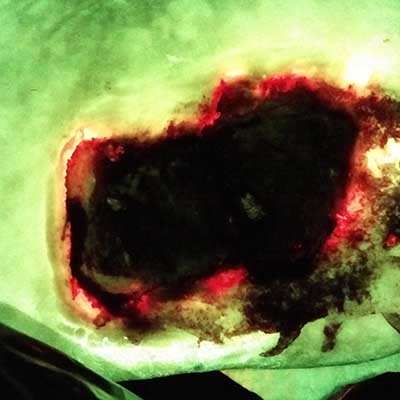

Skin Pigmentation Impacts the Clinical Diagnosis of Wound Infection: Imaging of Bacterial Burden to Overcome Diagnostic Limitations

Johnson J. et al. JREHD 2023

Bacterial Fluorescence Imaging to Address Racial Inequities in Wound Infection Assessment

Andersen, CA et al. Adv Skin & Wound Care 2024